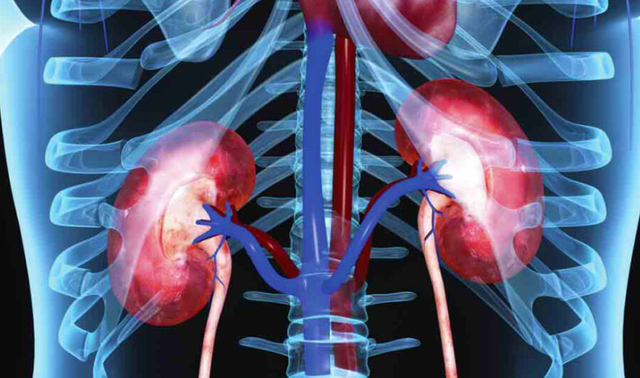

Veshkat janë organe jetike në trupin tonë. Ato janë përgjegjëse për filtrimin e gjakut, pastrimin e organizmit nga toksinat, prodhimin e hormoneve dhe ruajtjen e ekuilibrave të elektroliteve dhe lëngjeve në trup.

Veshkat kanë përgjegjësi të madhe por edhe janë të brishta, sidomos ndaj stilit të jetesës dhe veçanërisht ushqyerkes së keqe.